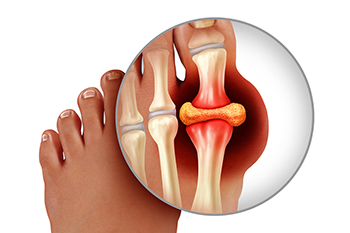

Gout is a form of inflammatory arthritis that often affects the joints of the toes, particularly the big toe. This happens when excess uric acid in the blood forms sharp crystals that deposit in the joints, leading to sudden and intense pain, swelling, and redness. Several factors contribute to high levels of uric acid. Dietary triggers such as red meat, seafood, and alcohol can increase uric acid production. Genetic factors also play a role, making some individuals more prone to developing gout. Certain medical conditions, including kidney disease, high blood pressure, and diabetes, can interfere with uric acid removal. A sedentary lifestyle or obesity further increase the risk. The toes are especially vulnerable due to their cooler temperature, which encourages crystal formation in that area. If you have symptoms of gout, it is suggested that you promptly contact a podiatrist who can help you to manage this painful condition.

What Is Gout?

Gout is a type of arthritis caused by a buildup of uric acid in the bloodstream. It often develops in the foot, especially the big toe area, although it can manifest in other parts of the body as well. Gout can make walking and standing very painful and is especially common in diabetics and the obese.

People typically get gout because of a poor diet. Genetic predisposition is also a factor. The children of parents who have had gout frequently have a chance of developing it themselves.

Gout can easily be identified by redness and inflammation of the big toe and the surrounding areas of the foot. Other symptoms include extreme fatigue, joint pain, and running high fevers. Sometimes corticosteroid drugs can be prescribed to treat gout, but the best way to combat this disease is to get more exercise and eat a better diet.